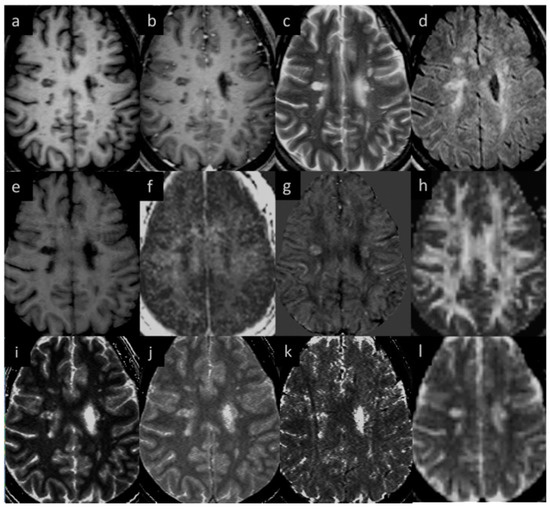

3.1. Lesions in MS Subjects

3.5. Correlation between Different Imaging Sequences